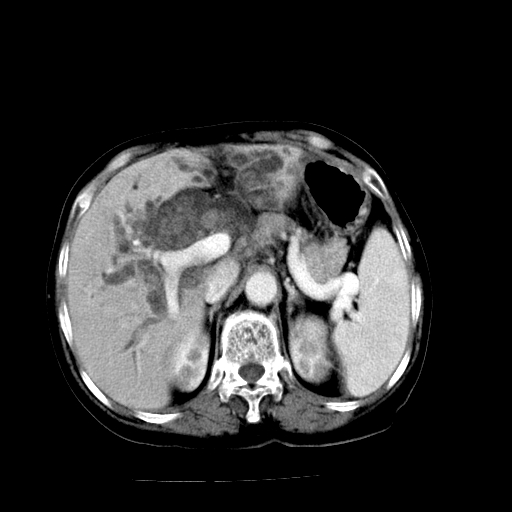

以下是引用随光逐影在2009-4-7 8:21:00的发言:[br]肝内外胆管多发性结石并肝内外胆管扩张;胆系感染。